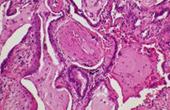

Гипертрофия миндалин – это медицинский термин для обозначения аномального увеличения ткани миндалин. Так как миндалины расположены в задней части горла, серьезные случаи этого состояния могут приводить к затрудненному глотанию и дыханию. Если слишком большие миндалины становятся проблемой, врач может рекомендовать корректирующую хирургическую операцию под называнием тонзилэктомия для удаления излишних тканей. Хотя некоторые люди рождаются с …